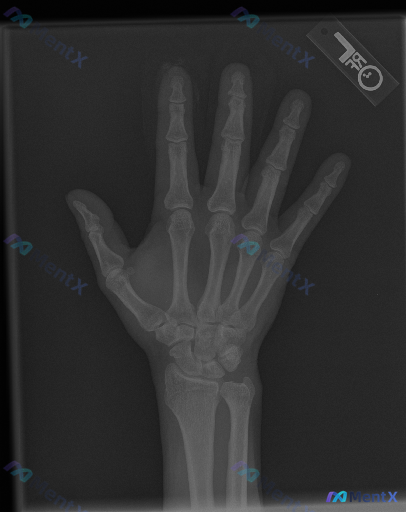

影像所见

- 骨皮质连续性:指骨、掌骨及腕骨骨皮质连续,未见明确骨折线、中断或台阶征;第一掌骨基底、第五掌骨颈区域也无异常

- 骨髓腔密度:骨小梁结构清晰,纹理分布均匀,未见局灶性骨质破坏、虫蚀样改变或明显异常硬化区

- 关节:各关节面平整,关节间隙清晰、宽度尚可,未见明显狭窄或不对称;腕关节、掌指关节对位良好,无脱位或半脱位;第一腕掌关节对合正常

- 软组织:手指及手掌周围软组织轮廓清晰,未见明显肿胀或局部增厚;无异常钙化或高密度异物残留

- 其他:各骨骺线已闭合,符合成年人骨骼特征;未见明确骨赘、边缘性骨侵蚀或普遍性骨质疏松等退行性/炎症性表现

影像层面给出的初步印象是「未见明显骨质损伤、脱位或显著的关节病变征象」,但临床场景预设「存在异常」。

📋答案:结合完整分析,这类「X光阴性但临床提示异常」的左手病例,应优先考虑**隐匿性创伤性病变**,同时需警惕早期感染性病变及非骨性软组织损伤的可能,避免因过度依赖X光阴性结果而漏诊。